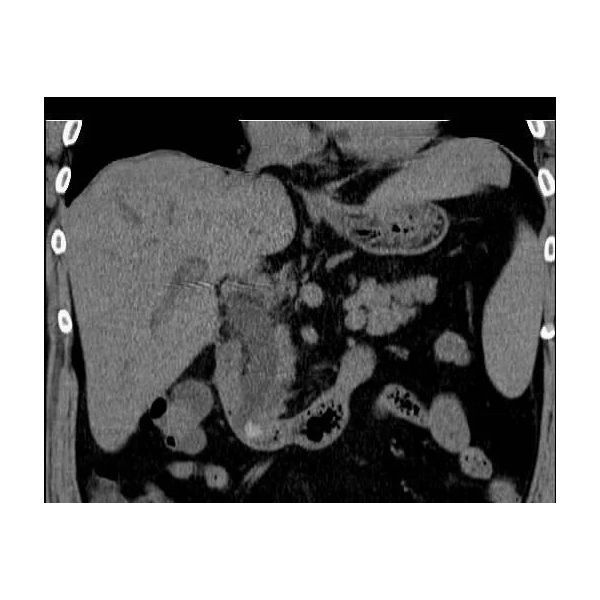

В ходе компьютерной томографии (КТ) обнаружены:

- выраженная билиарная гипертензия (повышенное давление в желчевыводящих путях);

- расширение холедоха, т. е. общего желчного протока (холедохоэктазия);

- признаки наличия двух камней диаметром до 2 см в нижнем отделе холедоха (холедохолитиаз), а также конкременты в желчном пузыре.